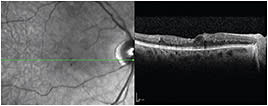

Given the eye’s lack of response to conventional laser treatment, the patient agreed to undergo MPLT. Prior to his MPLT session, his best-corrected visual acuity (BCVA) was 20/100-1, and CMT was 317 µm (Figure 1). I performed the treatment with the IRIDEX IQ 577™ (yellow) laser, incorporating the TxCell™ Scanning Laser Delivery System and a Mainster (standard) focal/grid contact lens. Delivering six 7x7 high-density grid patterns, I used 800 mW with a 5% duty cycle and used a 200-µm spot size and 200-ms duration. I no longer perform CW test burns in order to choose the power for my MPLT treatments. I’m able to select the power based on experience and patient presentation.

Figure 1. September 2012 | right eye | 8 months prior to MPLT CMT 317 µm | VA 20/100-1.